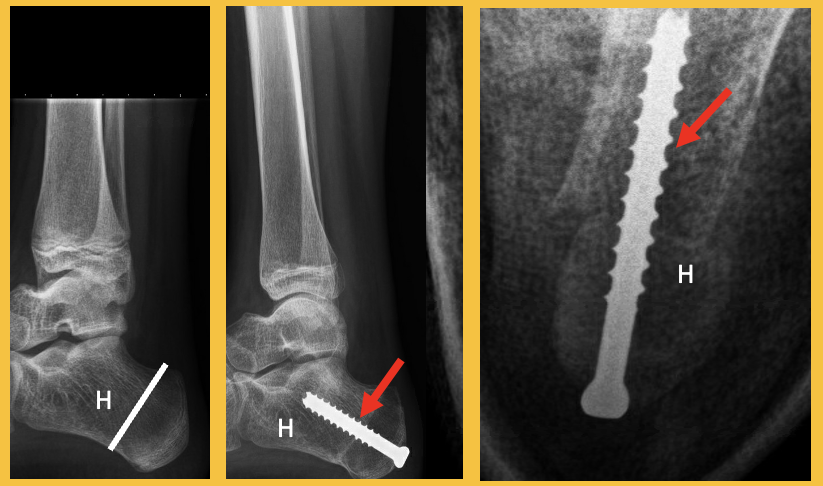

Solitaire Botcyste (SBC)

goedaardige bottumor

Een solitaire botcyste (SBC) is een goedaardige afwijking in het bot. Het is een met vocht gevulde holte in het bot. De binnenbekleding van de cyste bestaat uit fibreus bindweefsel. Lees in deze folder meer over de klachten en behandeling van deze afwijking in het bot.